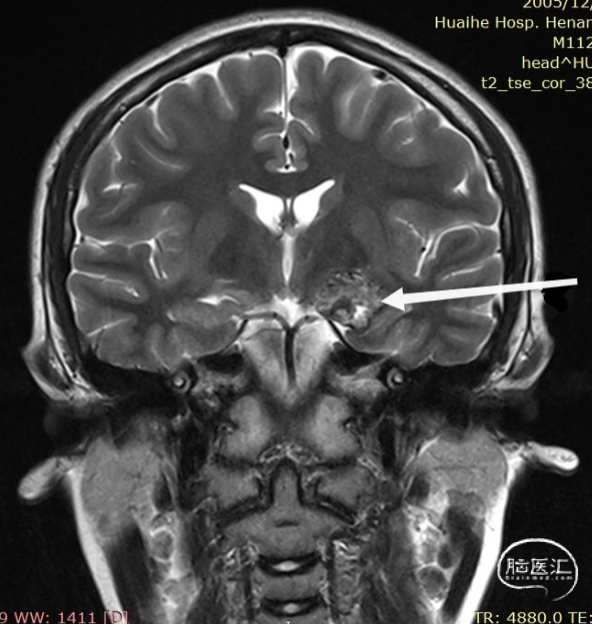

术前影像:

左侧海马旁回海绵状血管瘤。